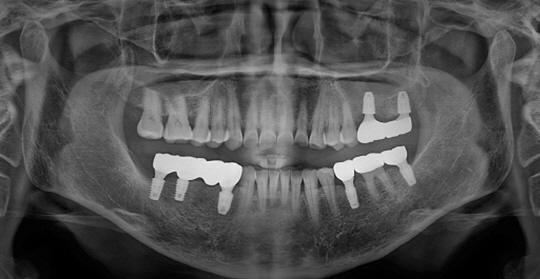

(66세 여 환자)

(38세 남 환자)

(61세 남 환자)

(50세 남 환자)

(63세 남 환자)

(59세 여 환자)

(67세 남 환자)

(45세 남 환자)